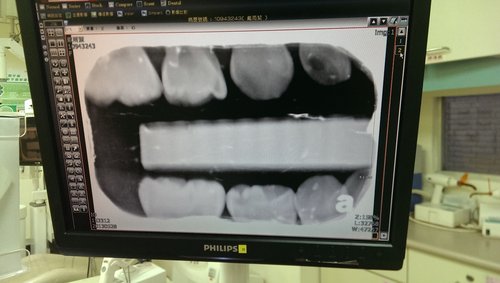

歐寶乖乖的讓醫生替他的牙齒照相,只是嘴巴含著東西很不舒服,所以歐寶一

直想吐

歐寶牙齒的照片~看得出來有蛀牙,之後要做溝隙填補!